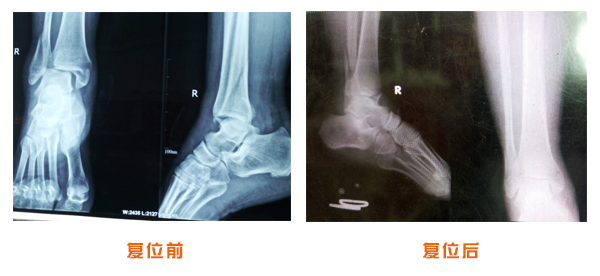

肥城市安駕莊梁氏骨科醫(yī)院是一所以梁氏手法正骨配合膏藥為特色的現(xiàn)代化專科醫(yī)院。

梁氏骨科術(shù)始創(chuàng)于清雍正年間,歷經(jīng)八代,至今已有三百年歷史。據(jù)1929年泰安縣志載“梁瑞圖先生,字增生,號蓮峰,安駕莊人,精岐黃并發(fā)明接骨,凡跌打車凡跌打車軋皮不破而碎骨者......【詳細(xì)】 |